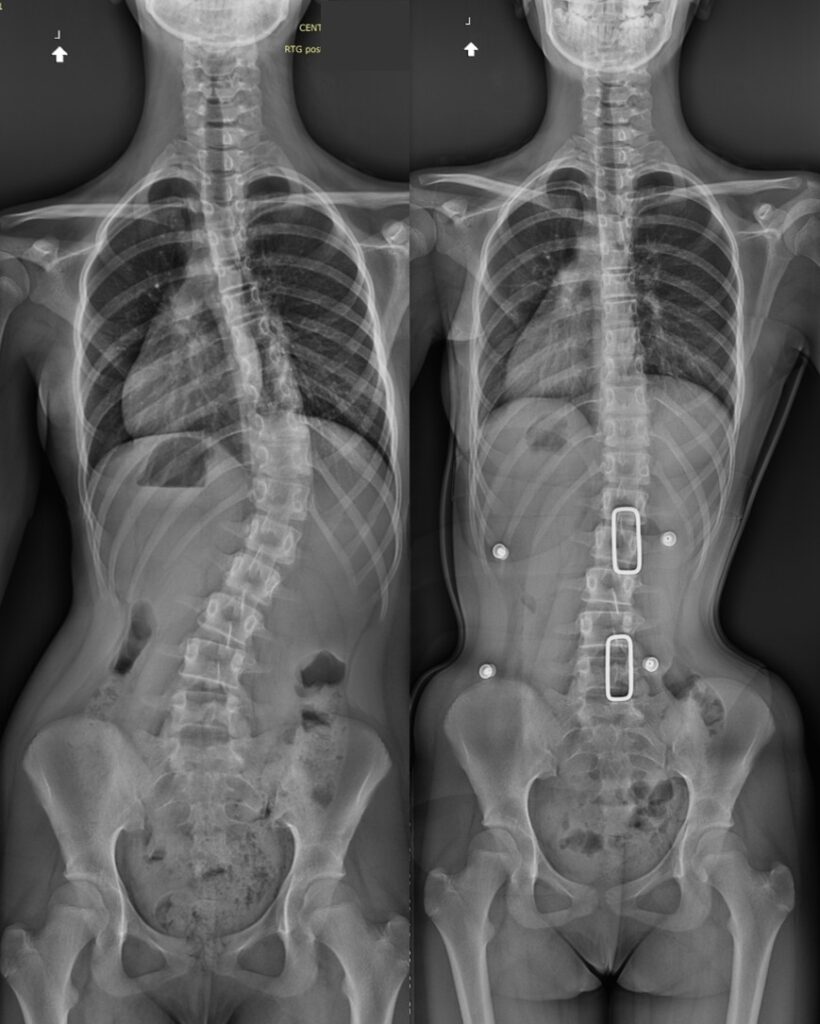

Jesteśmy rodzinną manufakturą ortopedyczną w Warszawie, specjalizującą się w tworzeniu indywidualnych wyrobów ortopedycznych na zamówienie. Projektujemy i wykonujemy gorsety ortopedyczne, buty ortopedyczne, wkładki, ortezy oraz protezy kończyn – wszystkie produkty powstają na podstawie dokładnych pomiarów pacjenta.

Oferujemy specjalistyczne szkolenie dotyczące stosowania gorsetu jako elementu leczenia zachowawczego pacjentów ze skoliozą oraz innymi schorzeniami kręgosłupa i klatki piersiowej.